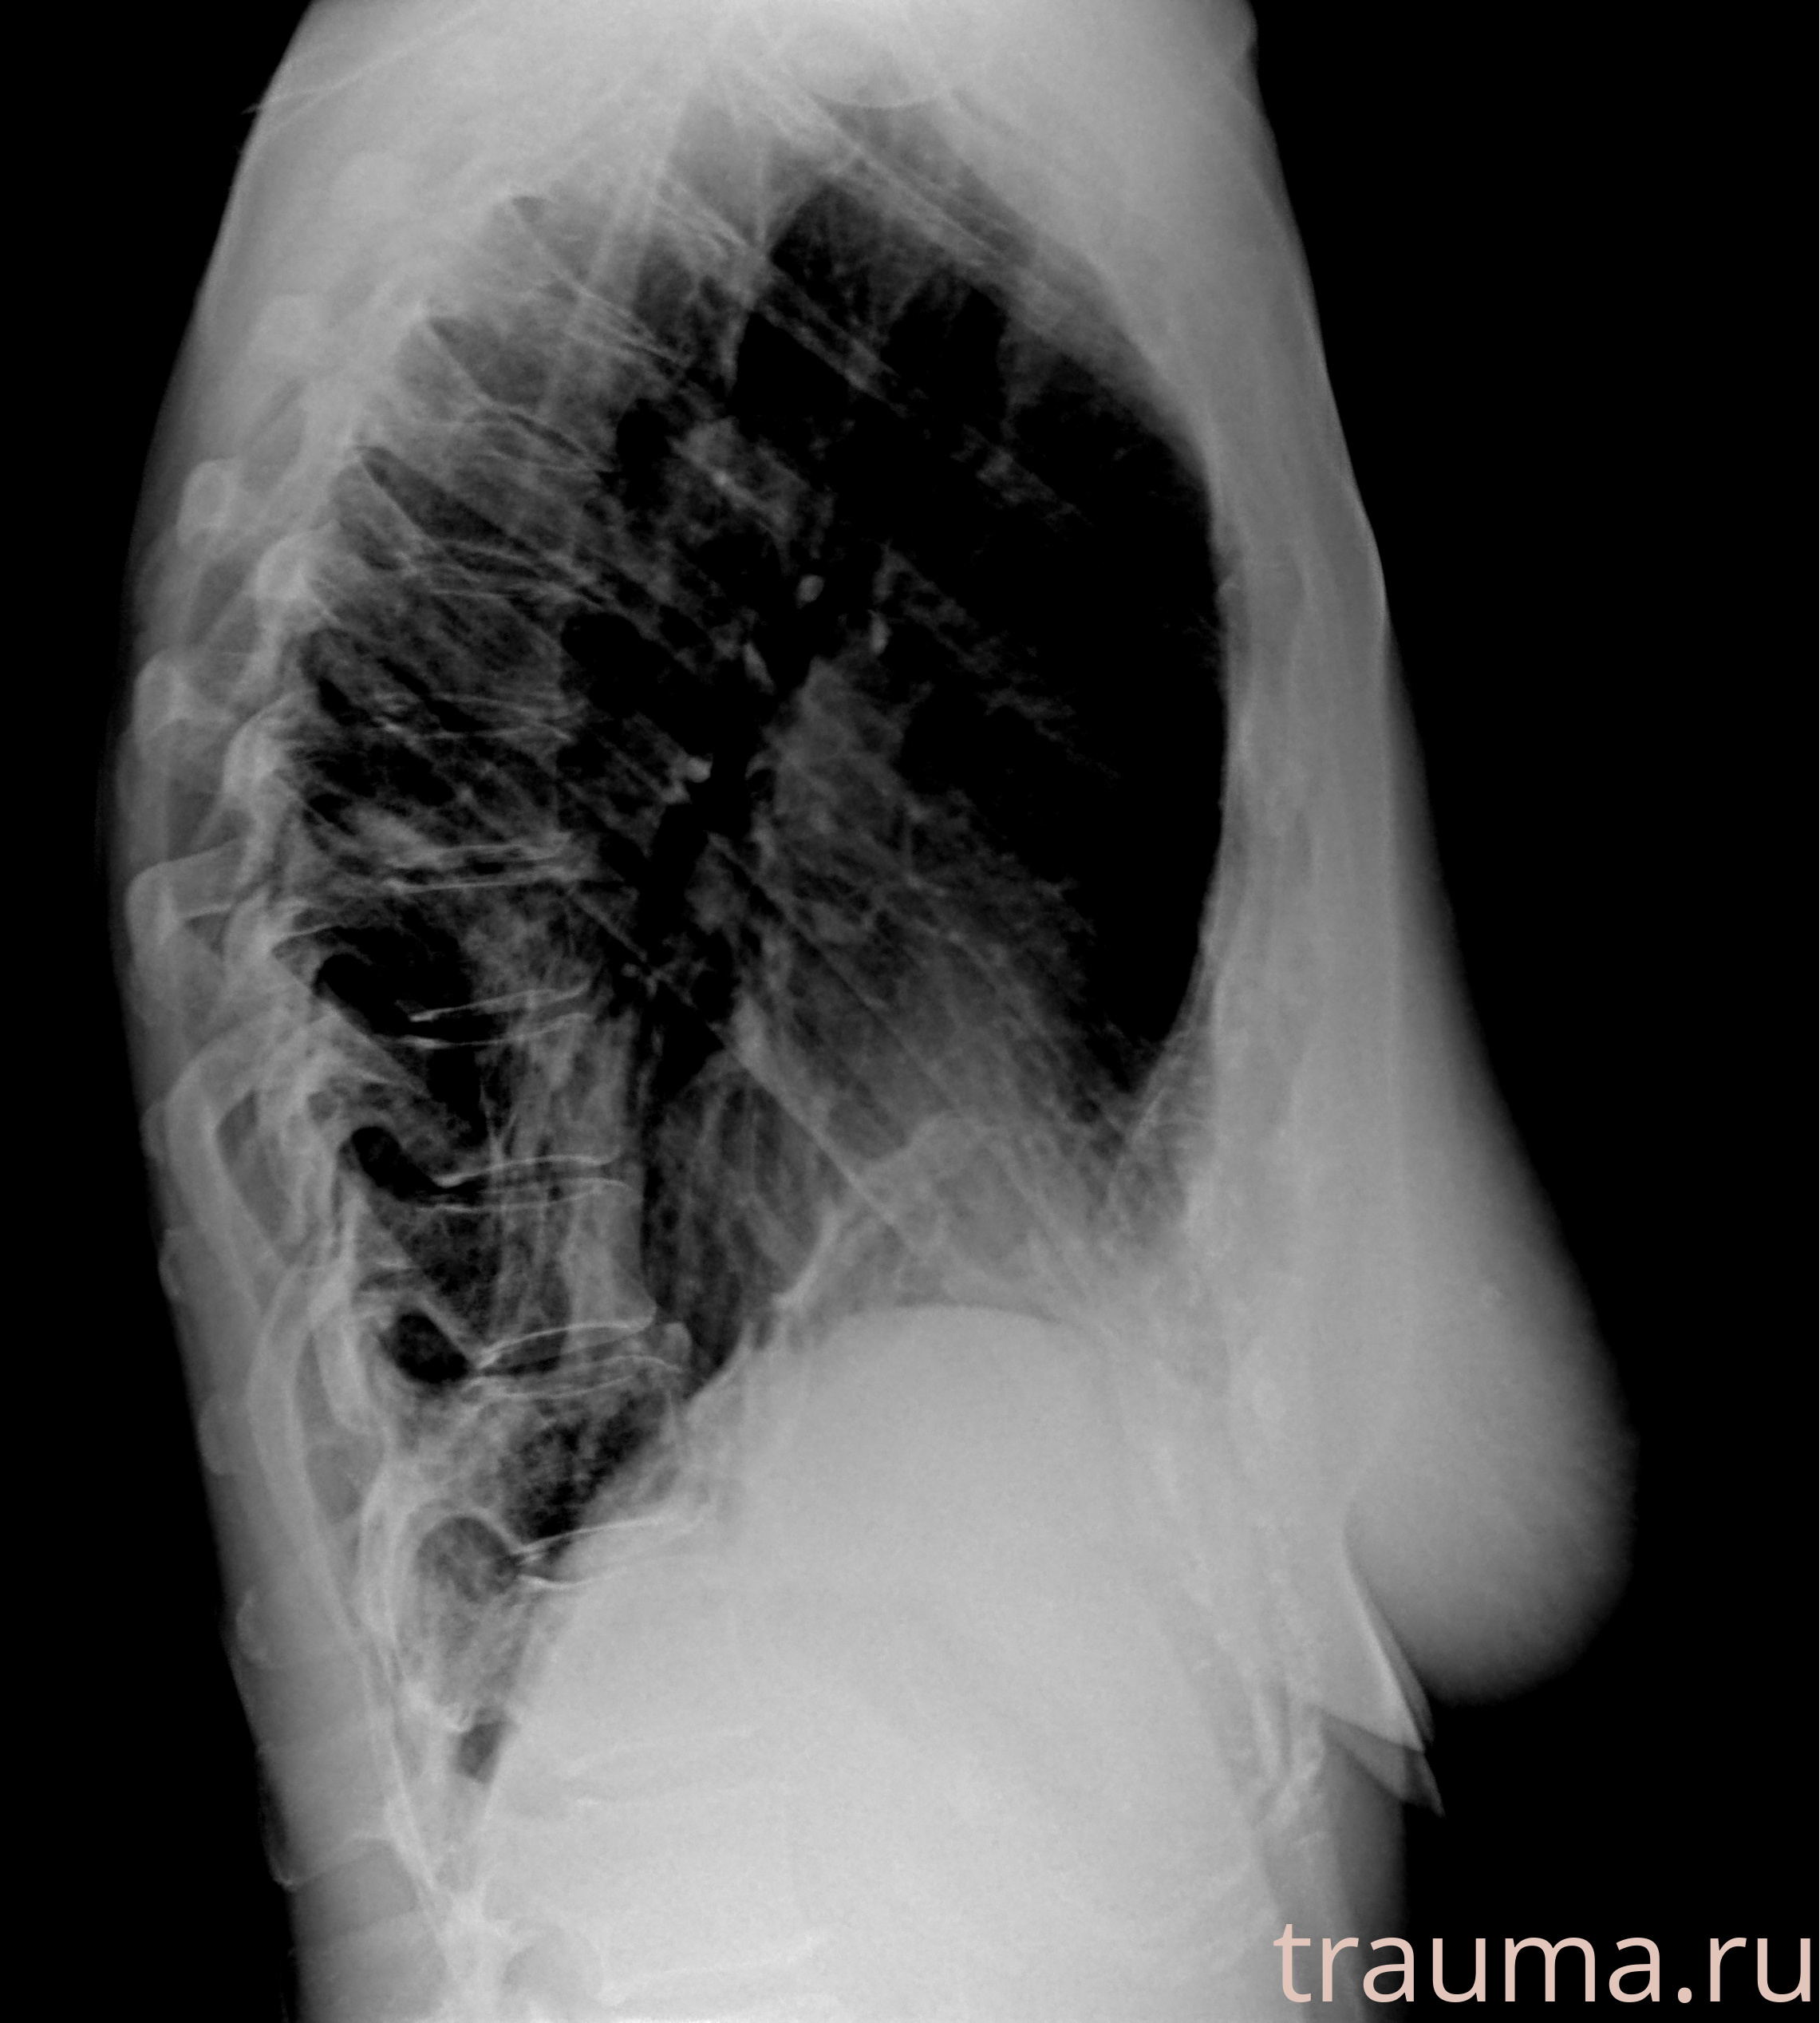

Рентген на дому: по вашему адресу приезжает врач-рентгенолог, травматолог-ортопед с мобильным рентгеновским аппаратом, проводит диагностику травмы или заболевания, делает необходимые рентгенограммы, дает рекомендации по дальнейшему лечению. Получить качественные снимки в домашних условиях возможно благодаря уникальной методике, разработанной МосРентген Центром для института  Склифосовского